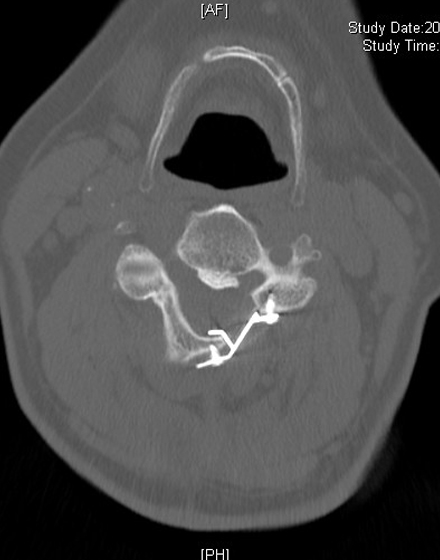

低侵襲脊椎側方固定術 XLIF (エックスリフ)、OLIF(オーリフ)

適応となる疾患:腰椎椎間板ヘルニア、腰部脊柱管狭窄症、腰椎変性すべり症、腰椎変性側弯症など

日本では2013年から承認されている低侵襲な脊椎側方固定術です。この手術は、トレーニングを受けた医師だけが実施できるため、全国でも限られた医療機関でのみ受けられます。当センターの日方医師は資格を有しているため実施可能です。この手術の最大の利点は脊髄神経を直接触らないで神経を圧迫から解除することにあります。側腹部に約5cmの皮膚切開により、下図のように神経機能を電気モニタリングで随時確認し重要な神経を避けながら椎間板内に人工骨を移植します。その後、腰部から固定術を行います。翌日から起立・歩行が許可され、入院期間は通常10~14日程度になります。